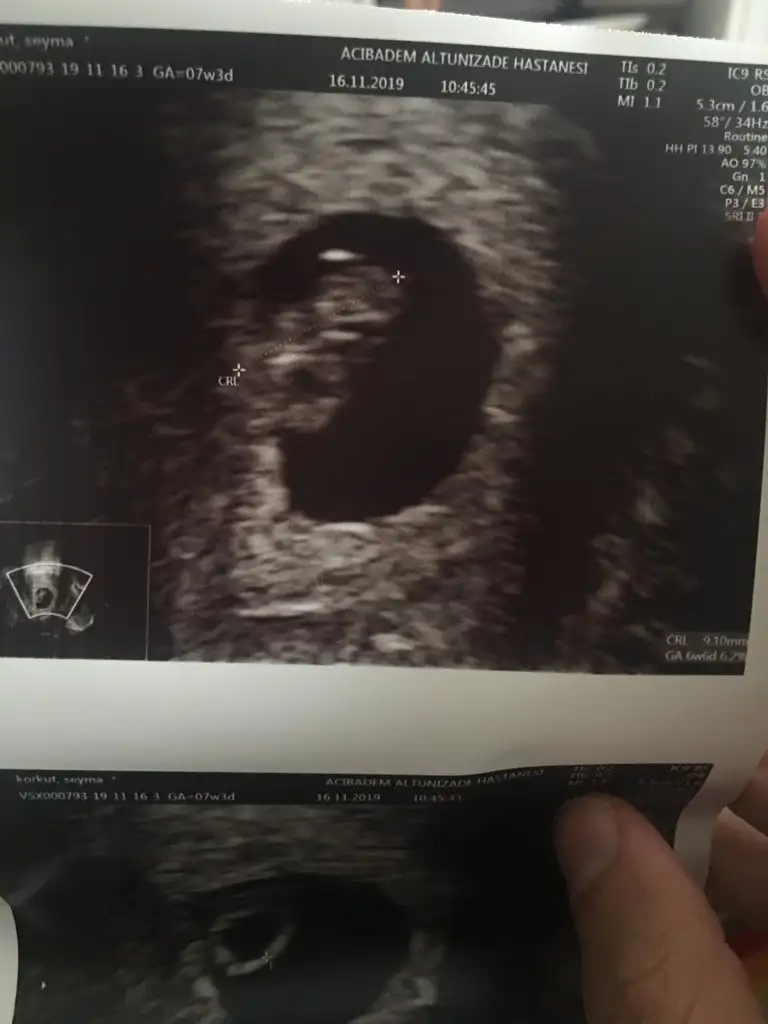

Kalp atışınini gördük cok şükür az da olsa duyduk da![]()

Maşallah darısı başımaKalp atışınini gördük cok şükür az da olsa duyduk da![]()

Hayırlı sağlıklı evlat olsunKalp atışınini gördük cok şükür az da olsa duyduk da![]()